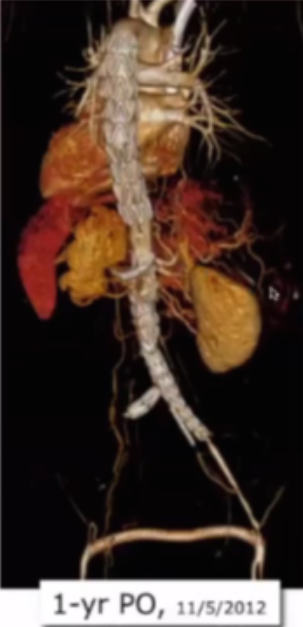

案例1:74岁男性患者,术前及6年瘤体的影像对比显示,动脉瘤瘤囊实现完全消退,体现出腔内治疗后长期的积极效果。

Complete aneurysm sac regression